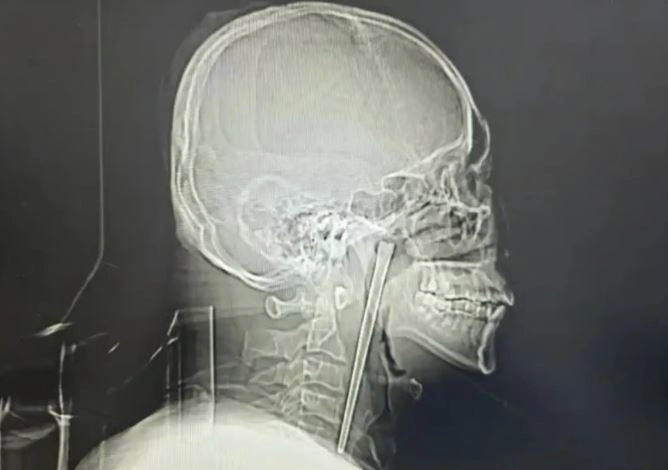

검사 결과 금속 젓가락은 목 안쪽에 박혀 있었으며, 주변 점막은 손상되지 않은 상태였다. 기관의 위치에도 이상이 없었고 성대 기능 역시 정상으로 확인됐다.

왕씨가 목 절개를 끝까지 거부하자 의료진은 입을 통해 이물질을 제거하는 최소 침습 수술을 시행했다. 수술은 큰 문제 없이 마무리됐으며 출혈도 거의 없었던 것으로 전해졌다. 길이 12cm의 금속 젓가락은 무사히 제거됐고, 왕씨는 수일 뒤 퇴원했다.